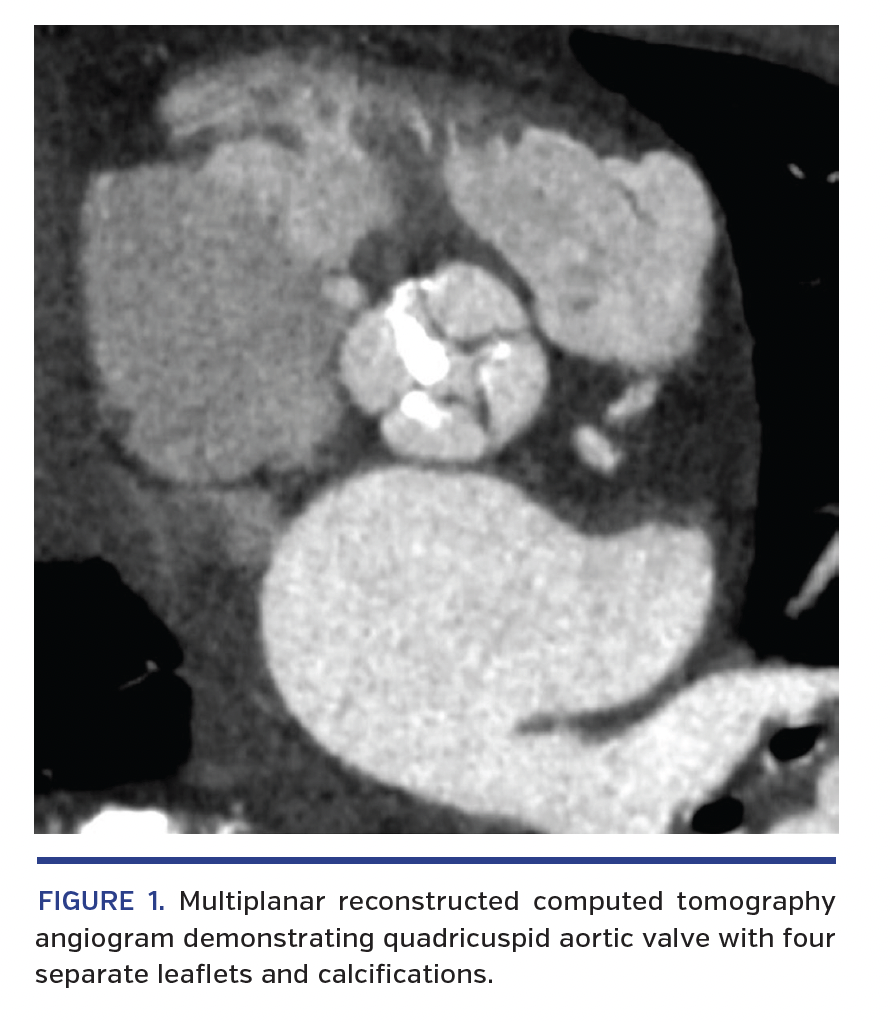

A heart team evaluation recommended minimalist approach transfemoral transcatheter aortic valve implantation (MA-TF TAVI). Preprocedural computed tomography angiography revealed a quadricuspid aortic valve (QAV) with four separate leaflets (Figure 1).